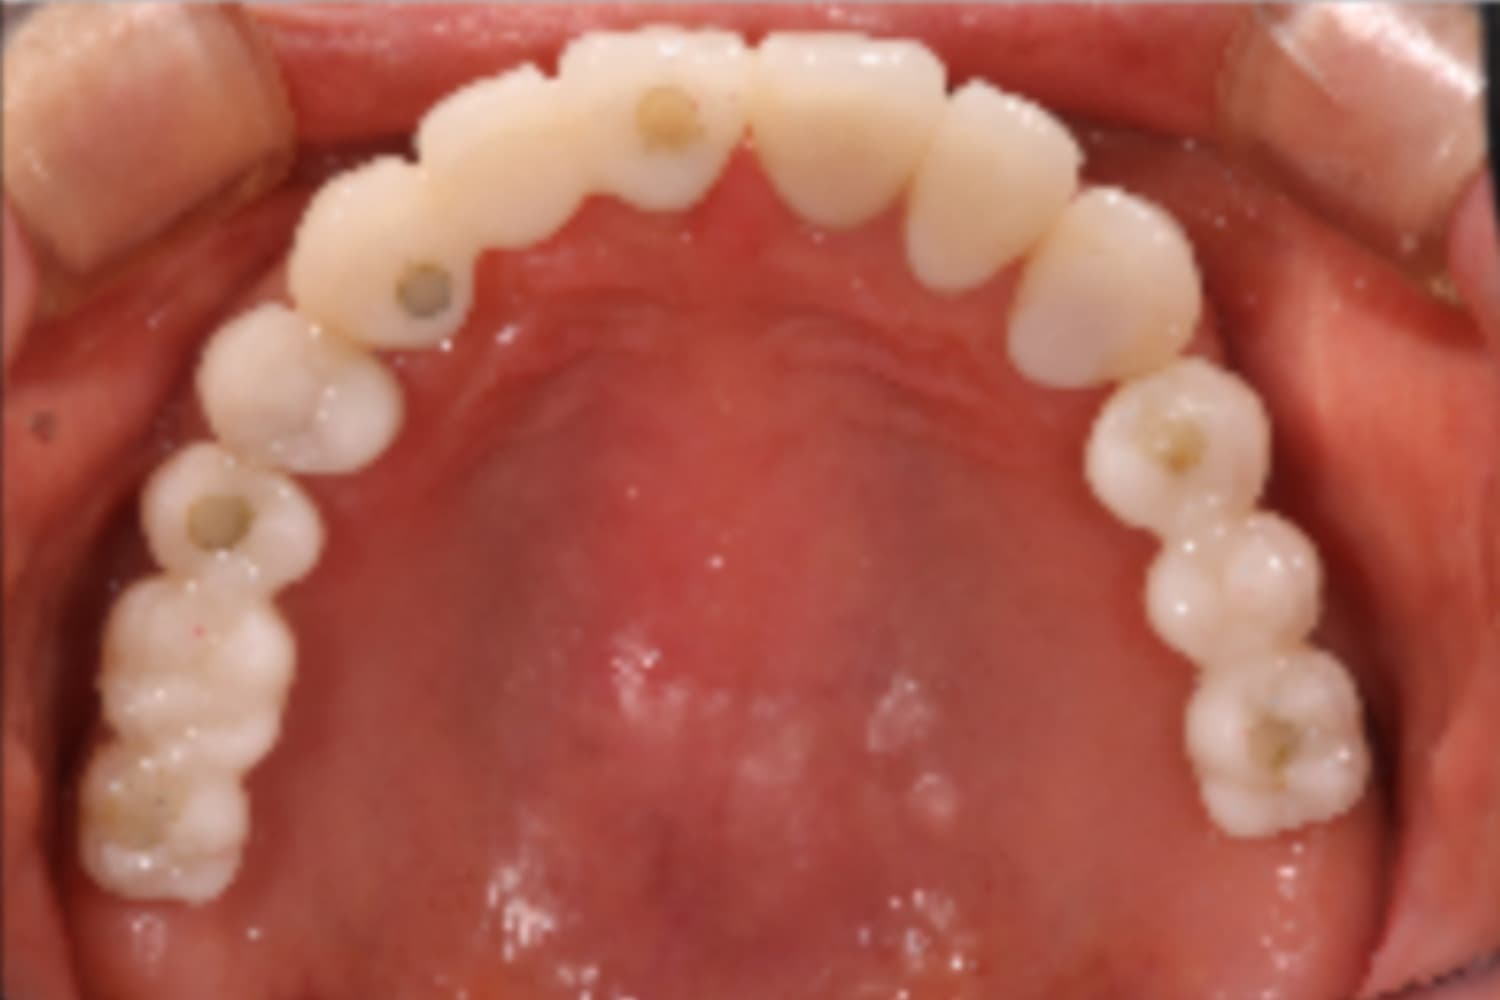

上顎すべてのインプラント治療

Before

After

上顎をインプラント7本で治療

主訴

上顎欠損部にインプラント治療希望

治療期間

18カ月

治療回数

26回

費用

3,450,000円

副作用・リスク

・噛み合わせの崩壊により、治療途中に顎の痛みや顎関節症様の発症リスクがあります。